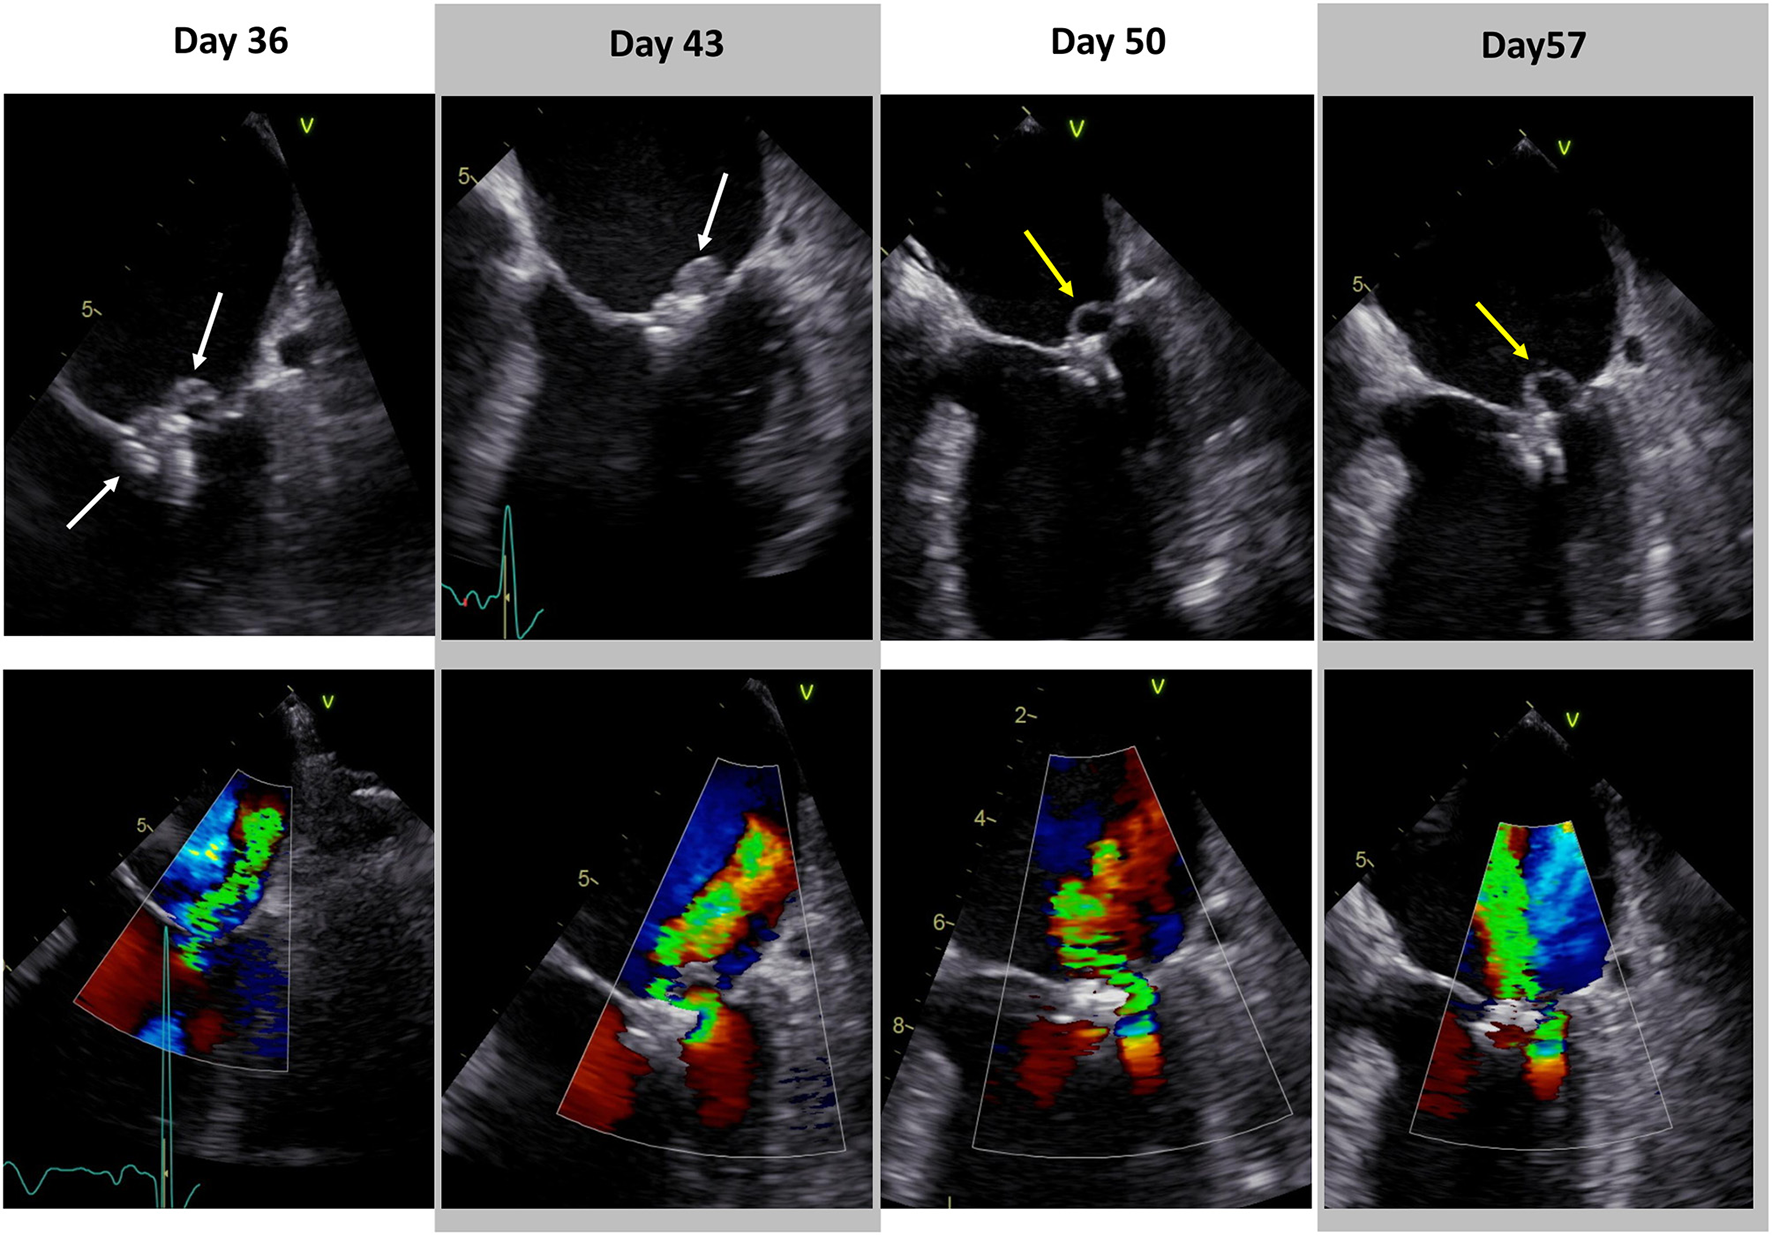

Figure 2

Progress of infective endocarditis in transesophageal echocardiography. Transesophageal echocardiography of infective endocarditis at various timepoints during calculated antibiotic therapy. Day 0 = transcatheter mitral valve edge-to-edge repair. White arrows indicate vegetations. Yellow arrows show perforated posterior mitral leaflet and significantly reduced vegetation (Day 36: Supplementary Videos 3, 4; Day 43: Supplementary Videos 5, 6; Day 50: Supplementary Videos 7, 8; Day 57: Supplementary Videos 9, 10).

The antibiotic regimes with Ampicillin were continued and transesophageal echocardiography (TOE) was scheduled. In TOE, IE of the PASCAL Ace device was confirmed by a vegetation accompanied by a mild to moderate mitral regurgitation (Figure 2, Day 36; Supplementary Videos 3, 4). Patient was transferred to the Cardiology ward and the local endocarditis team (infectious disease specialist, cardiologist, microbiologist and radiologist) contacted the cardiac surgeon to discuss explantation of the PASCAL Ace device. Risk score evaluation resulted in a very high operative risk (logEuroscore: 37.1%, Euroscore 2: 5.3%, STS score mortality: 5.3%). While the patient was stable at this time and deemed not suitable for cardiac surgery, the endocarditis team made a decision toward a prolonged 6-week antibiotic regime with an antibiotic combination of Ampicillin 2 g qds and Ciprofloxacin 750 mg td. The choice for Ciprofloxacin was based on its high tissue accessibility. Weekly TOEs were performed (Figure 2; Day 43: Supplementary Videos 5, 6; Day 50: Supplementary Videos 7, 8; Day 57: Supplementary Videos 9, 10). Figure 3 shows the inflammatory markers over the clinical course starting at the timepoint of TEER (day 0). Due to posterior leaflet perforation severe mitral regurgitation developed while PASCAL Ace vegetations were significantly reduced by the antibiotic therapy. Therefore, together with the patient and his relatives, the Endocarditis Team made the decision to perform high risk cardiothoracic surgery. On day 69 the patient underwent successful endoscopic mitral valve replacement with a bioprothesis (St Jude Medical Epic 33 mm, Abbott Vascular, Santa Clara, CA, USA; Figure 4). The second day after the operation the patient was free of catecholamines and extubated. The post-operative histology confirmed ulcerative endocarditis, while microbiological culture of the resected tissue was culture negative for bacterial growth. Another four weeks of antibiotic treatment with Ampicillin 2 g qds followed, which was oralized on day 89. The patient was discharged to rehabilitation on day 90. The final echocardiographic result after minimal-invasive mitral valve replacement showed a good post-operative result. Patient was recommended to have lifelong endocarditis prophylaxis.